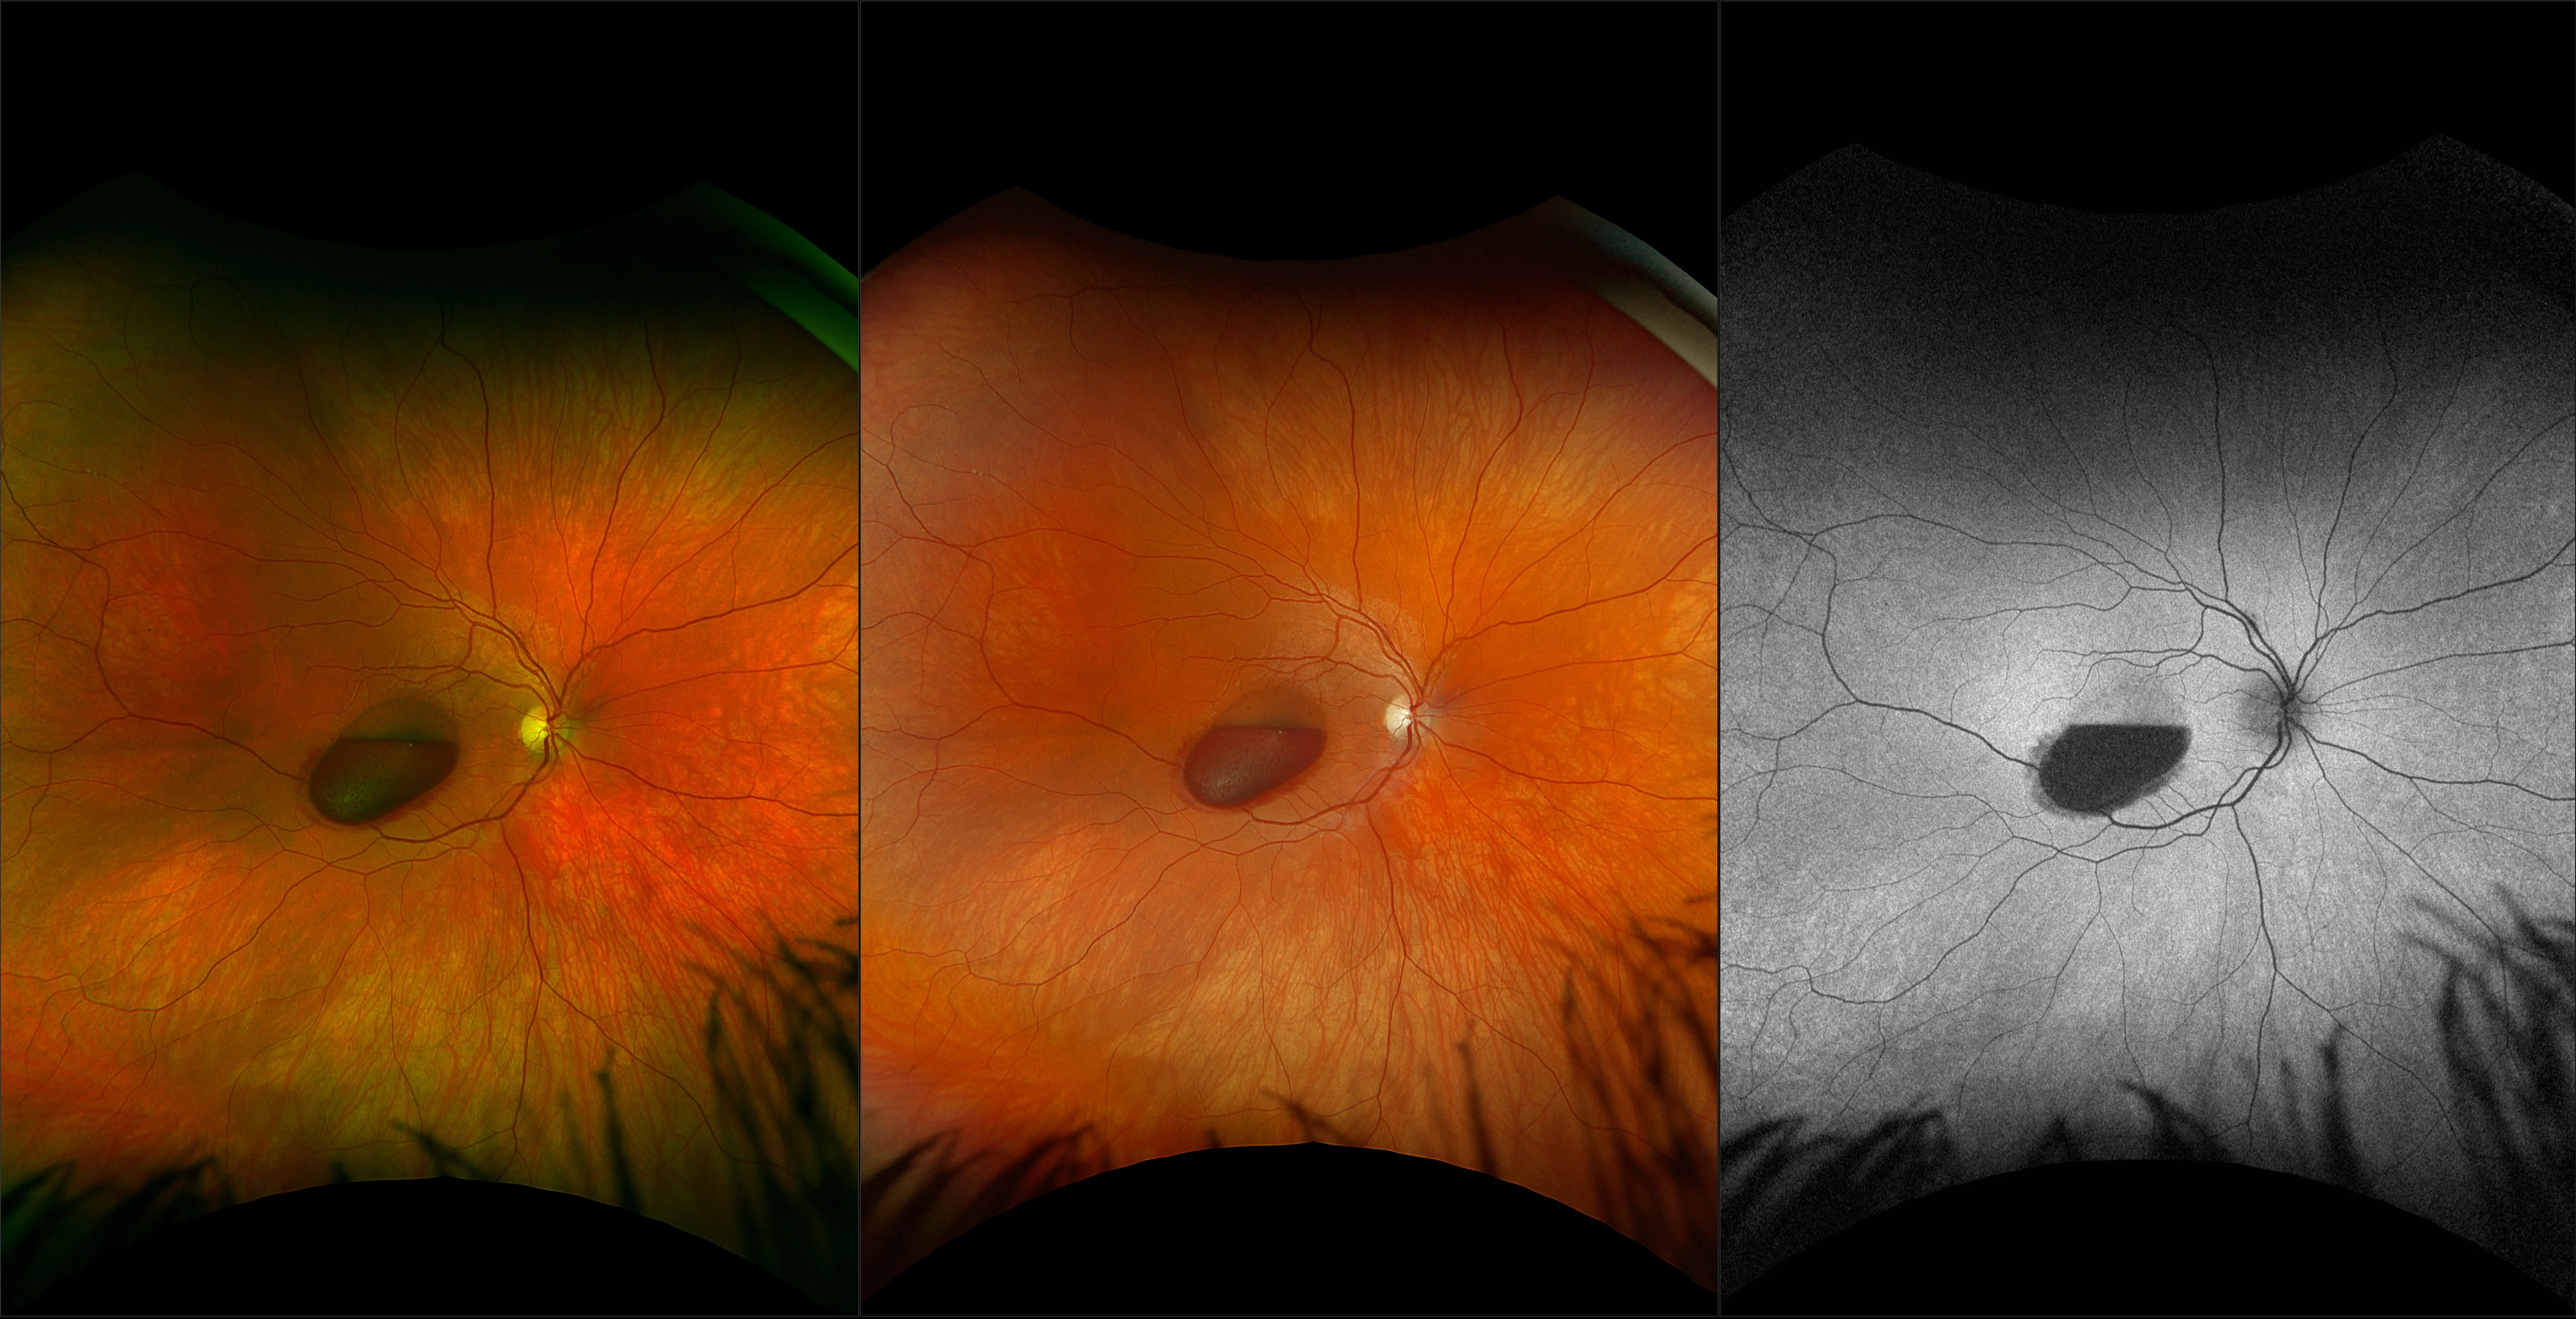

optomap® Recognizing Pathology

This material is designed as a searchable reference resource to support clinical decision-making. The information contained here should be used as general guidance when viewing optomap and OCT images from Optos devices. The differential diagnosis should be made under the direction of the responsible physician. These images were taken on the latest ultra-widefield optomap devices.

The Cases and Images

optomap Recognizing Pathology is searchable by pathology and/or optomap image modality. You may search by multiples of each selection. Each individual case is represented by the accompanying thumbnail image. Most cases include several different optomap image modalities. To view a full description of the case, please click on the thumbnail. Each image in the case will be made available through our OptosAdvance software which provides multi-dimensional visualization of digital images to aid in the analysis of anatomy and pathology. Support and pathology definitions can be found by selecting one of the buttons, above. Should you have questions, please complete the form below.